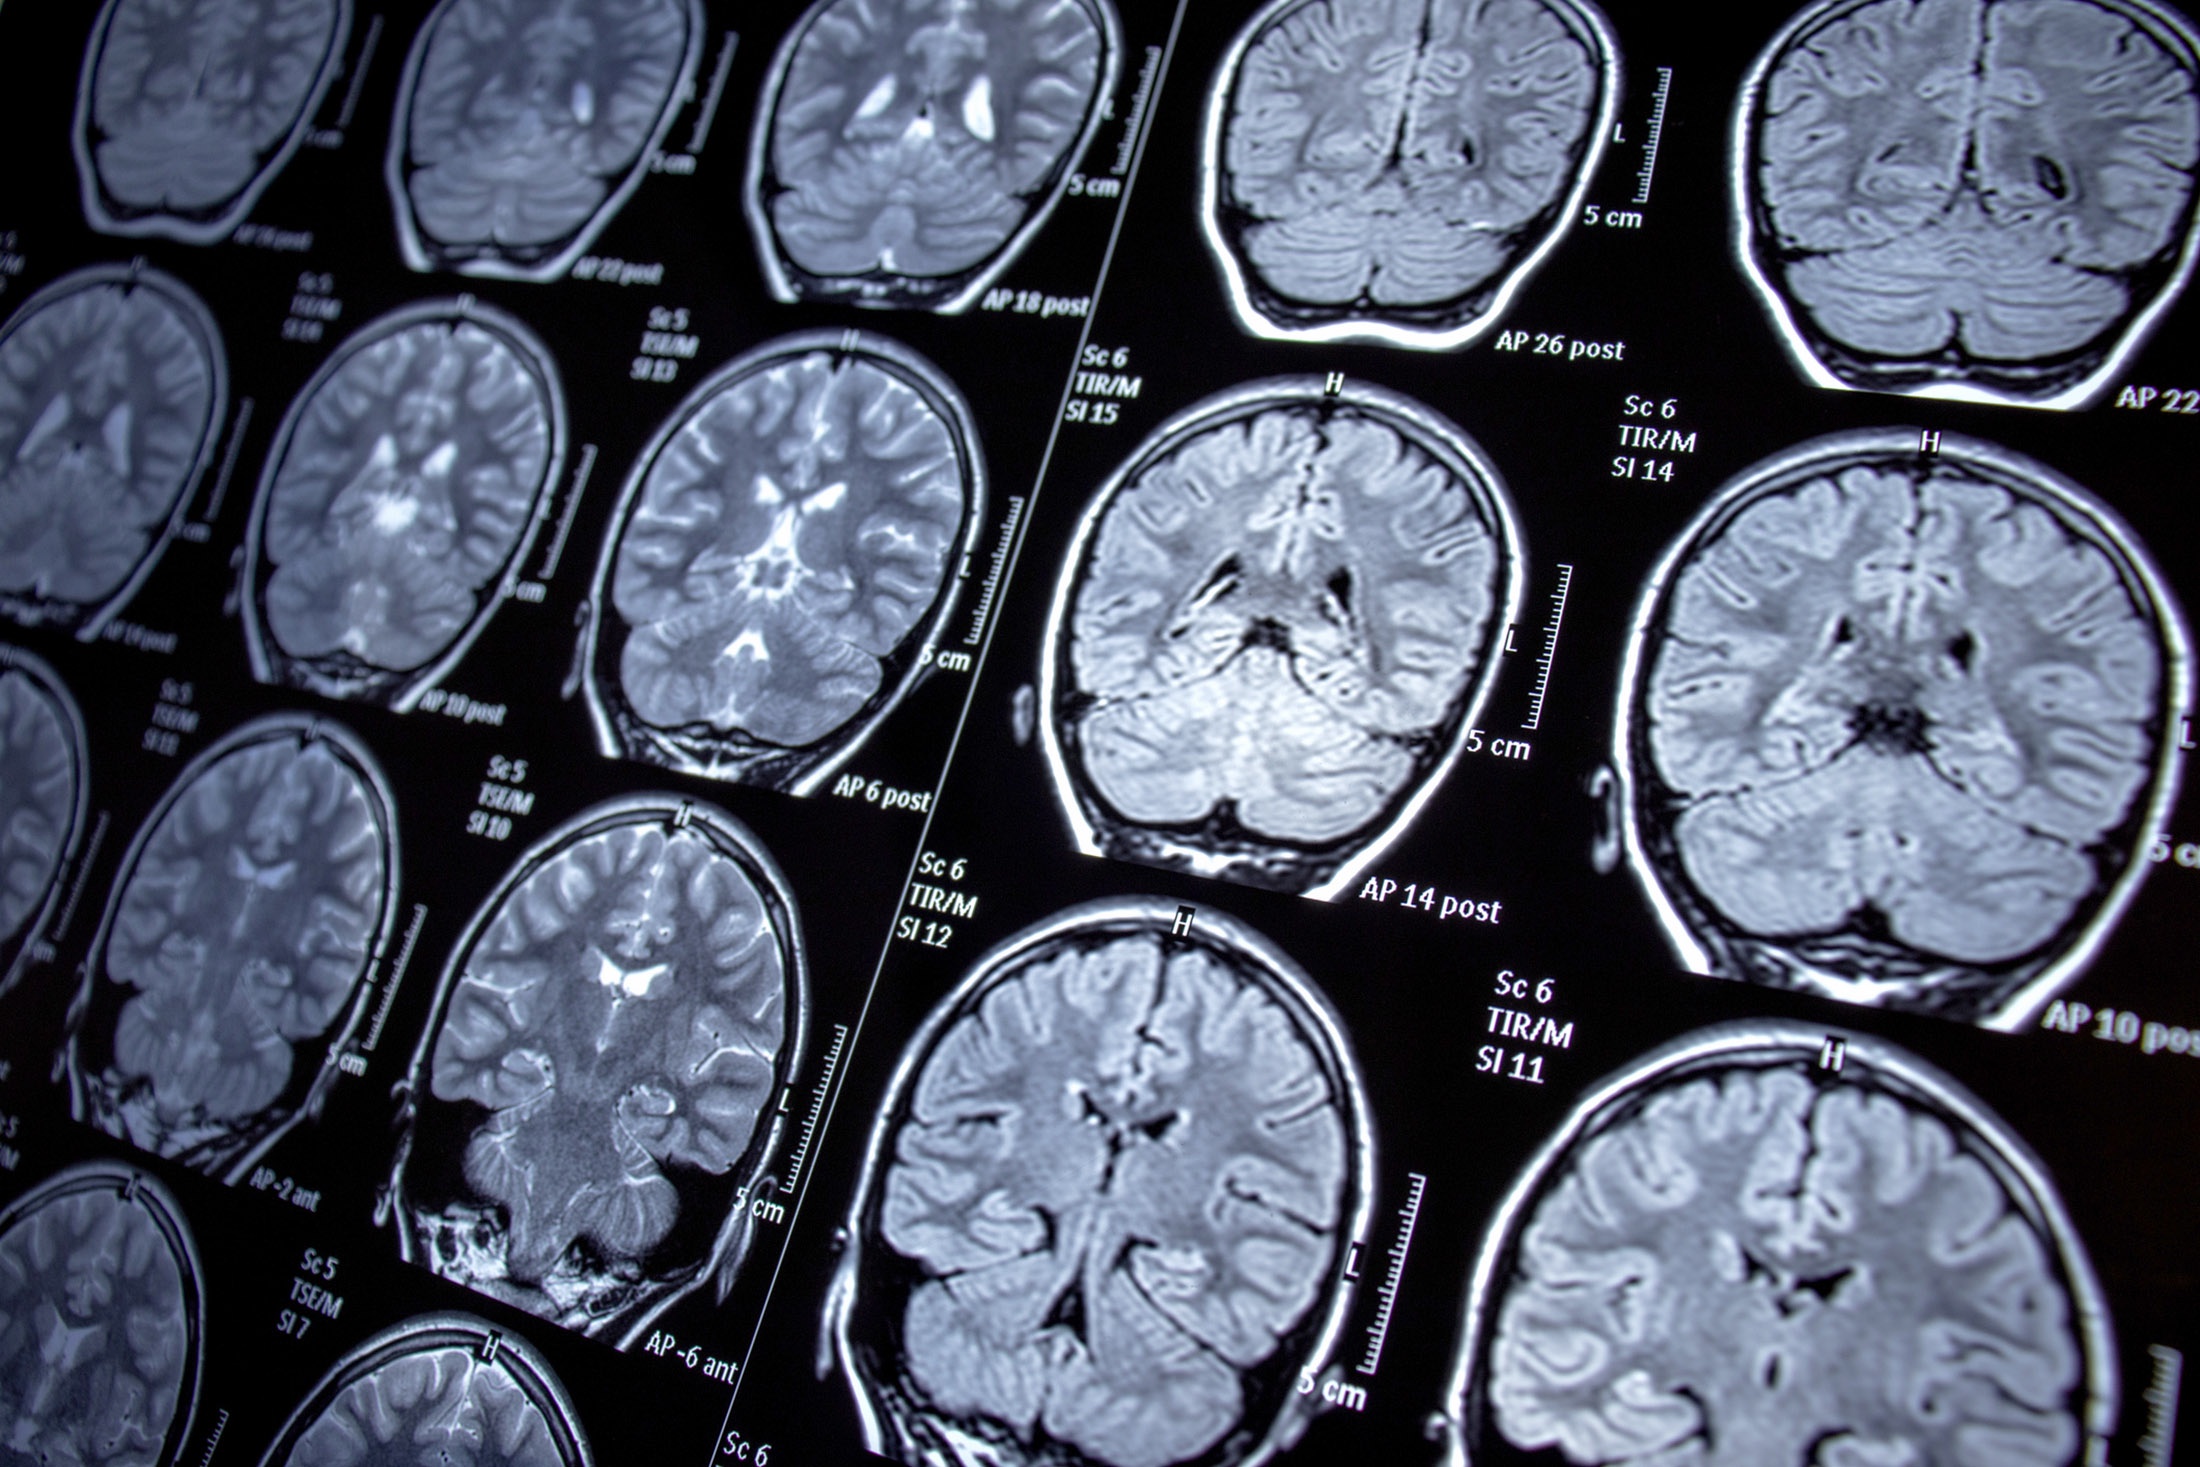

Развивающиеся с возрастом нейродегенеративные заболевания - болезни Альцгеймера, Паркинсона - традиционно считаются необратимыми. Усилия ученых направлены в основном на разработку лекарств и методов, лишь замедляющих процесс нейродегенерации. Однако специалисты Института нейронаук и нейротехнологий Пироговского Университета оттолкнулись от предположения, что наш мозг может изначально обладать способностью противостоять процессам разрушения мозга.

Дарья Серебряная: Нейродегенерация - это непрерывный процесс гибели нервных клеток в головном и спинном мозге, который влечет за собой необратимые нарушения памяти, движения и мыслительных способностей. Это ключевой механизм для множества заболеваний, обусловленных как генетическими факторами, так и возрастными изменениями под влиянием внешней среды.